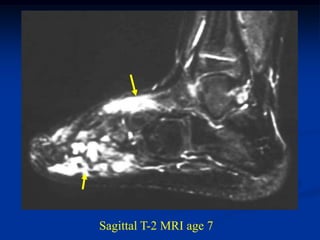

CLASSIC        Case #254

2 month male with infantile fibromatosis right leg

AP                       LAT

Dysplastic bowing fibula at age 2 years

Progressive changes at 7 years

Sagittal T-1 MRI at 7 years

Sagittal T-2 MRI age 7